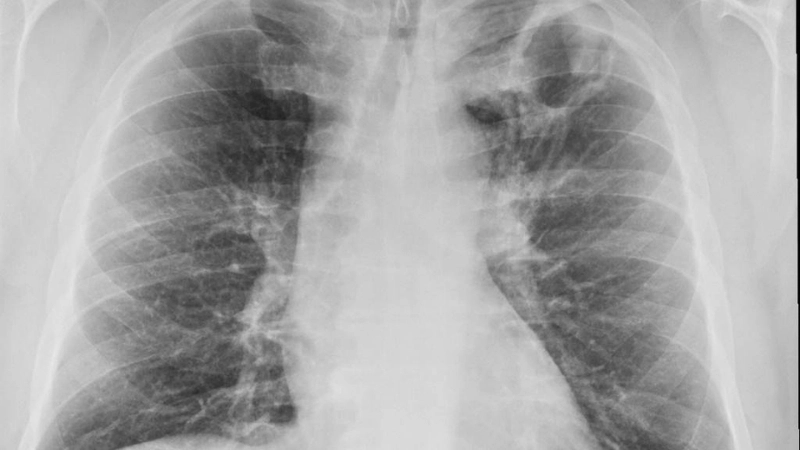

Chẩn đoán hình ảnh bệnh lao phổi qua các phương pháp phổ biến

Tổng quan các hình ảnh bệnh lao phổi thường gặp